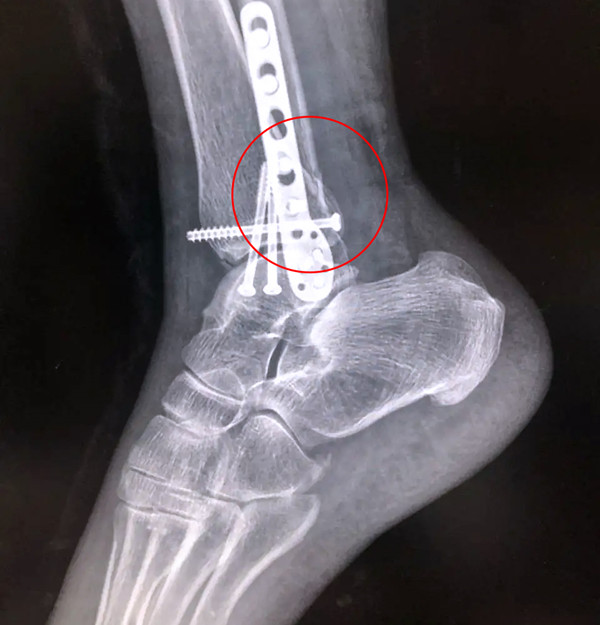

有一種特殊類型的踝關節(jié)骨折,可能在X影像平片上就不能顯示出來,它就是脛骨的關節(jié)面往里塌陷,我們又稱之為叫“Pilon骨折”。當它往里塌陷后,我們在X影像平片上可能看不出來它是否塌陷,但是我們在CT上可以360°看到踝關節(jié)的影像,這樣就可以看出患者是否存在踝關節(jié)塌陷的骨折。同樣道理,我們在做Pilon骨折手術的時候,普通二維的X影像并不能判斷我們手術復位情況的好壞,這個時候如果醫(yī)生手上有能夠照三維影像的工具,那么對于醫(yī)生的準確手術是非常有好處的。

三維影像 助力復雜手術準確治療